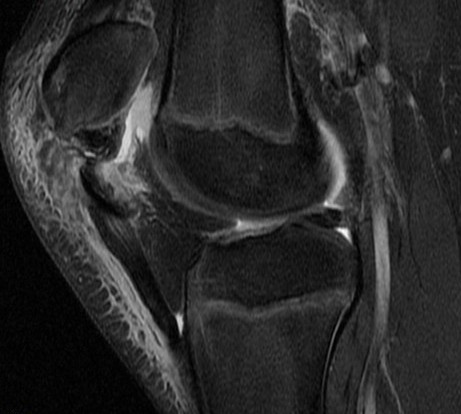

Trampoline injury, 10y/o

Wheeless: mechanism: eccentric contraction of the quadriceps on the flexed knee. occurs when the inferior pole of the patella of a child or adolescent is pulled off together with a large amount of articular cartilage and retinaculum. Superior patella pulled superiorly with chondral defect. Reference article.

Patellar sleeve avulsion